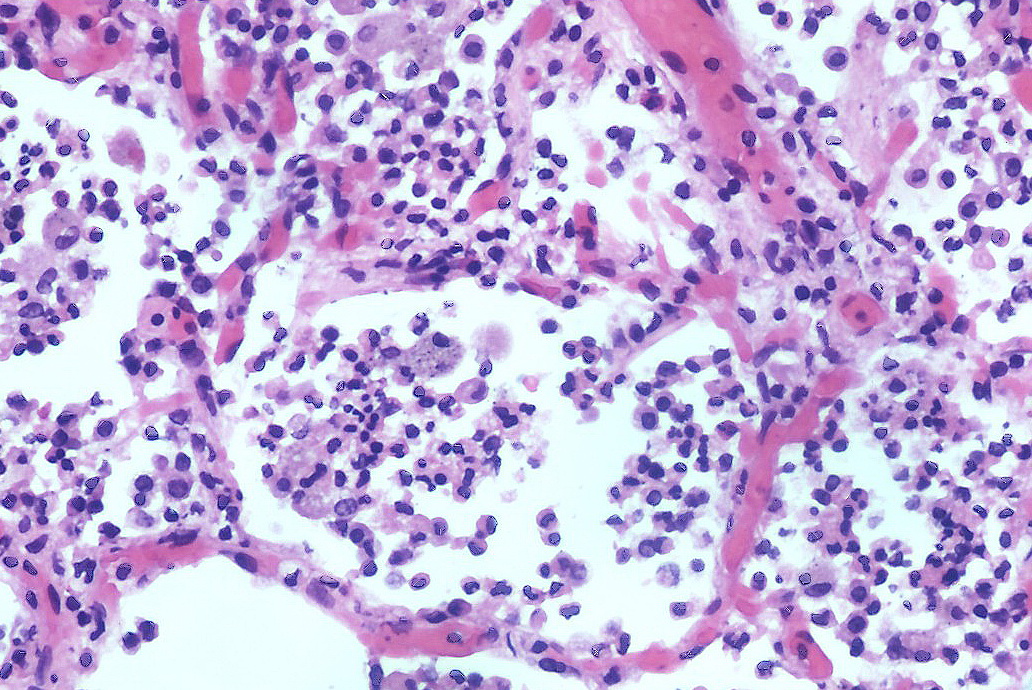

Cercetătorii au creat un tip de roboți microscopici înotători pentru a elimina microbii care provoacă pneumonie din plămânii șoarecilor, rezultat care îi face pe experții să spere că un tratament similar ar putea fi dezvoltat pentru a trata pneumonia mortală la oameni.

Microboții sunt realizați din celule de alge și acoperiți cu un strat de nanoparticule de antibiotic. Algele asigură mișcarea prin plămâni, ceea ce este esențial pentru ca tratamentul să fie eficient.

Nanoparticulele de pe celulele algei sunt alcătuite din sfere mici de polimer acoperite cu membranele neutrofilelor, un tip de celule albe din sânge. Aceste membrane neutralizează moleculele inflamatorii produse de bacterii și de propriul sistem imunitar al organismului, iar atât nanoparticulele, cât și algele se degradează în mod natural.